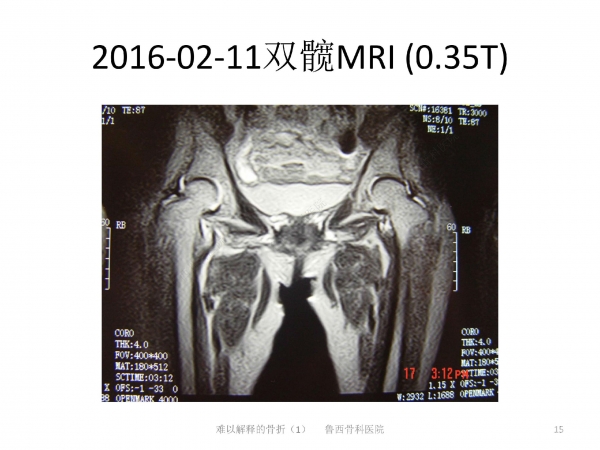

导语:在日常生活中,因老年人普遍存在骨质疏松的问题,滑倒很容易造成髋部骨折。90%的老年人发生髋部骨折多因摔倒引起。然而有些骨折完全没有外伤,前驱疼痛,属于不典型骨折。来自鲁西骨科医院的王书军医师、段玉民医师,为我们带来一例“难以解释的骨折”病例,并做了初步探讨。请详见下文分解。